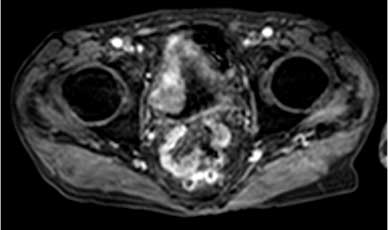

Hình 4. Hình ảnh có thuốc tương phản giai đoạn sớm ở cùng bệnh nhân như hình 2 và Hình 3 thể hiện sự bắt thuốc mạnh của nửa trong của thành bàng quang

Khi khối u có sự bắt thuốc, cần đánh giá kỹ để xem xét liệu đây là độ dày tất cả hay ít hơn một nửa độ dày của thành bàng quang để cung cấp giai đoạn về phương diện X quang (Hình 4). Niệu quản xa có thể thấy sự bắt thuốc nếu như khối gần với lỗ niệu quản (Hình 5).